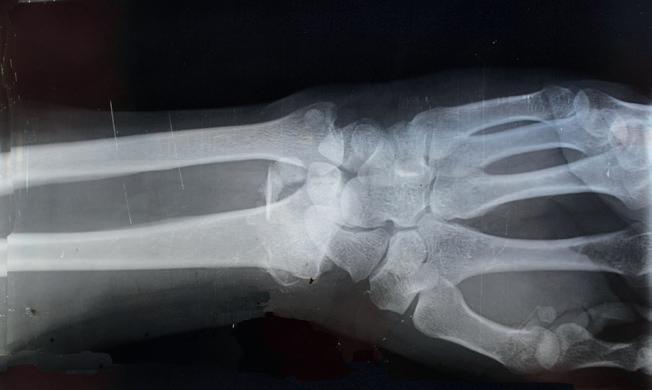

Osteoporosis is a "silent disease" that causes bones to weaken, becoming more susceptible to fractures even from minimal impact. It occurs gradually over many years without your knowledge. So, the only way to know how strong your bones are is to have a scan known as a bone densitometry scan as until about the age of 30, we produce bone faster than we lose it, but around the age of 40 it tends to plateau. After this time, the reverse is true and bone mass declines and for women this bone loss is particularly accelerated during the menopause.

The Achilles bone density test is a non-invasive test that offers a quick and affordable way for an initial osteoporosis assessment and the risk of bone fractures. The exam is quick and comfortable and is performed with the patient seated with one foot placed on the Footplate. The machine uses high frequency sound waves to evaluate the os calcis (bone status in the heel), The patient will receive the results immediately from the specialist performing the test.

Remember it is never too early to start looking after your bones so book your Achilles Bone density test here at Clinica Britannia as soon as possible.